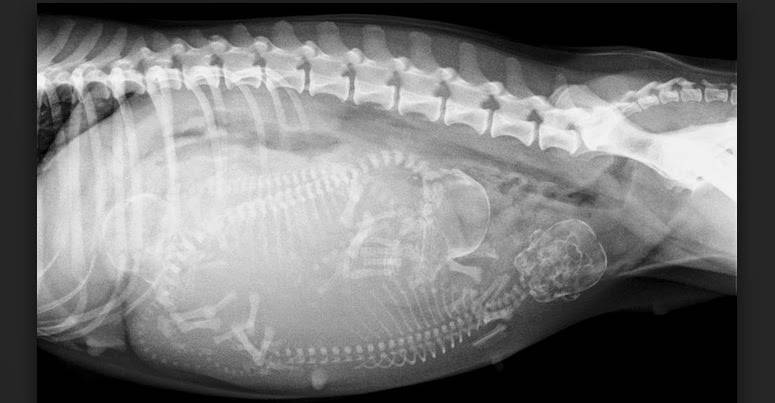

Помимо осмотра, пальпации и сдачи анализа крови, диагностика предполагает проведение УЗИ и рентгена. Эти процедуры помогают определить точное количество и состояние плодов, но не раньше начала 2-го месяца.

Ветврачи настоятельно рекомендуют с помощью рентгена проверять на количество щенков молодых сук, у которых первая беременность.

- Обследовать потомство рентгеном можно на 45 день, так можно определить, сколько именно щенков ждет сука.

- Рентгенография. Ее следует делать не ранее 42-45 суток, когда костная система щенков будет полностью сформирована. Исследование позволяет оценить расположение щенков, их размеры и количество.